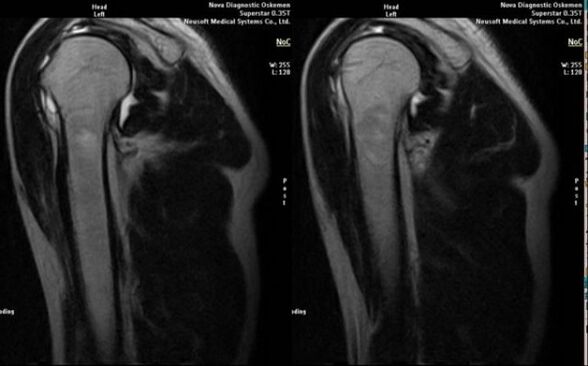

- magnetic resonance and computed tomography;

Signs that directly indicate the development of arthrosis are the appearance of a significant narrowing of the joint space, sclerosis of subcartilaginous structures, thinning of the chondrocyte layer itself, the appearance of osteophytes and the deposition of salt crystals in the intra-articular fluid.